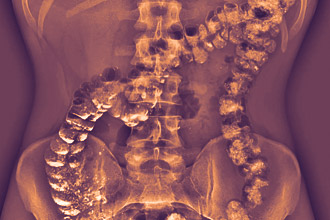

Ирригоскопией называется один из методов рентгенологического исследования толстого кишечника, при котором контрастное вещество вводится в орган через анальное отверстие. Далее заданная область просвечивается с целью выявления болезней, патологий и проблем. Подготовка к ирригоскопии кишечника проводится в домашних условиях и начинается за 3 дня до планируемого сеанса. Алгоритм проведения манипуляций согласовывается с врачом, так как возможны нюансы. Соблюдение правил необходимо не только для повышения информативности подхода, но и для облегчения самого процесса осмотра.

Проведение ирригоскопии после подготовки, сделанной по всем правилам, занимает от 15 до 45 минут в зависимости от ее целей. Все инструменты и контрастный раствор готовятся специалистом заранее. Жидкость подогревается до 35ºС, проверяется исправность аппарата. Непосредственно перед началом манипуляции врач проводит ректальный осмотр и после его положительных результатов приступает к сеансу.

- В прямую кишку вводится наконечник аппарата Боброва, через который подается смесь. Все действия врача контролируются рентгеноскопией.

- Далее пациент меняет позу, чтобы контрастная масса распределилась по кишечнику.

- Снимки делаются по мере заполнения нижних отделов пищеварительного тракта. Последний снимок делается уже после того, как орган будет полностью заполнен.

- Далее аппарат вынимают из кишечника, после чего пациент должен его опорожнить. Теперь специалист делает еще один снимок, с помощью которого можно будет оценить состояние слизистой органа и его функциональной активности.

- Наступает последний этап обследования, который называется двойным контрастированием. В пустой кишечник нагнетают воздух, который расправит складки органа. На его эпителии остается контрастная взвесь, позволяющая оценить состояние стенок до мельчайших подробностей. На снимках после этого будут видны полипы, опухоли и даже маленькие язвочки.